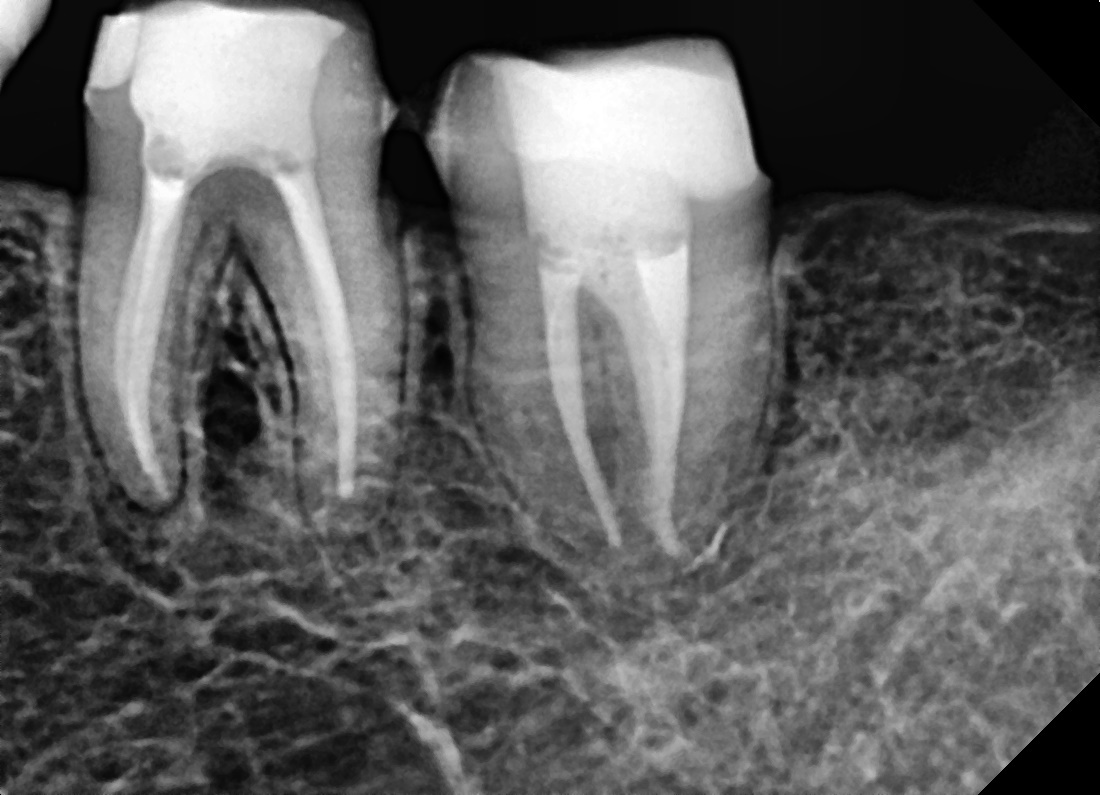

치근단병소 치유

심한 염증으로 고름이 찬 어금니

Before

After

치료 6개월 후 치근단병소 완전 치유